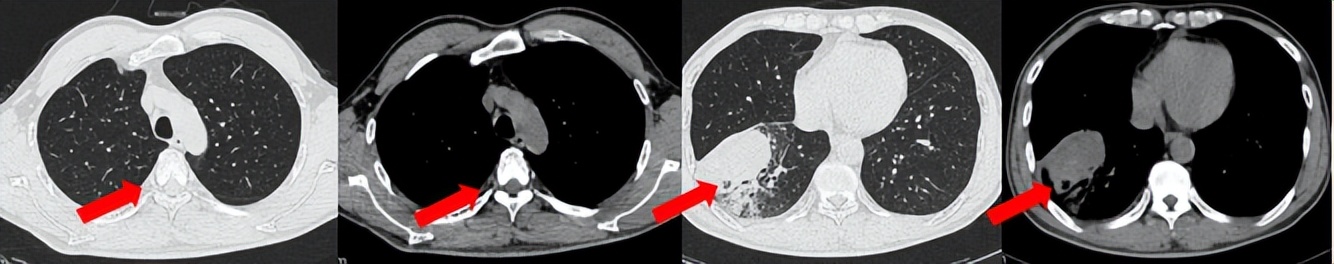

治疗经过:2024.08开始口服赛普替尼(160mg,bid)。2024.09复查胸CT评效PR。2025.1复查胸CT:右肺下叶外基底段见一不规则形实性肿块,大小约94mm×87mm,边缘呈分叶状,其内密度不匀。右侧胸腔见少许水样密度影。评效PD,PFS=5个月。患者未同意再次组织活检,目前应用卡博替尼治疗,仍在随访中。治疗期间未出现毒性反应。

2024.08

2024.09评效PR

2025.01评效PD